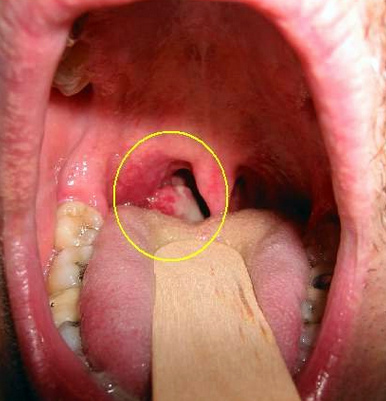

Рак горла, фото начальная стадия:

Врачи отмечают, что начальная стадия рака горла часто протекает бессимптомно, что затрудняет его раннюю диагностику. Многие пациенты не обращают внимания на легкие дискомфорты, такие как охриплость или незначительные боли в горле, что может привести к запущенным формам заболевания. Специалисты подчеркивают важность регулярных осмотров и внимательного отношения к своему здоровью. При наличии подозрительных симптомов, таких как длительная охриплость или затрудненное глотание, необходимо незамедлительно обращаться к врачу. Ранняя диагностика значительно увеличивает шансы на успешное лечение и полное выздоровление. Врачи рекомендуют также избегать факторов риска, таких как курение и злоупотребление алкоголем, что может снизить вероятность развития заболевания.